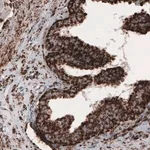

Prestige Antibodies® 라인의 CL3771 클론 단일클론 항체로, 인간 SLCO1B3 단백질을 인식합니다. 정제된 IgG1 형태의 1차 항체이며, 면역조직화학에 적합합니다. −20°C에서 보관하며, 습한 얼음 상태로 배송됩니다.

Prestige Antibodies® Powered by Atlas Antibodies, clone CL3771.

| Technique(s) | Immunohistochemistry (1:500–1:10000) |